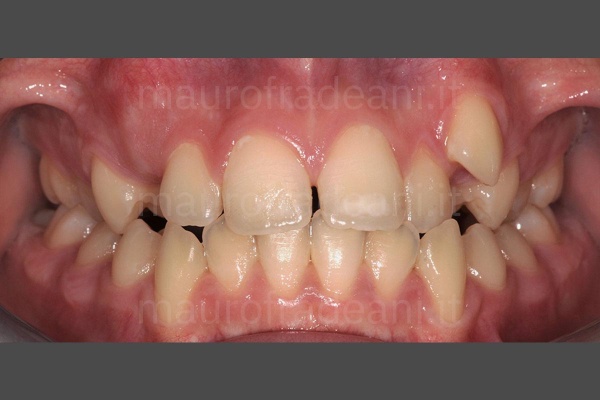

Pre-prosthetic orthodontics

1/5: The patient presents severe dental crowding with misalignment of the lower incisors, dental shape and volume alteration with enamel wear of the gingival collars and worn incisal margins causing esthetic and functional issues. Before treating this case with prosthetic restorations, a preventive orthodontic realignment is necessary.

2/5:

3/5:

4/5:

5/5: